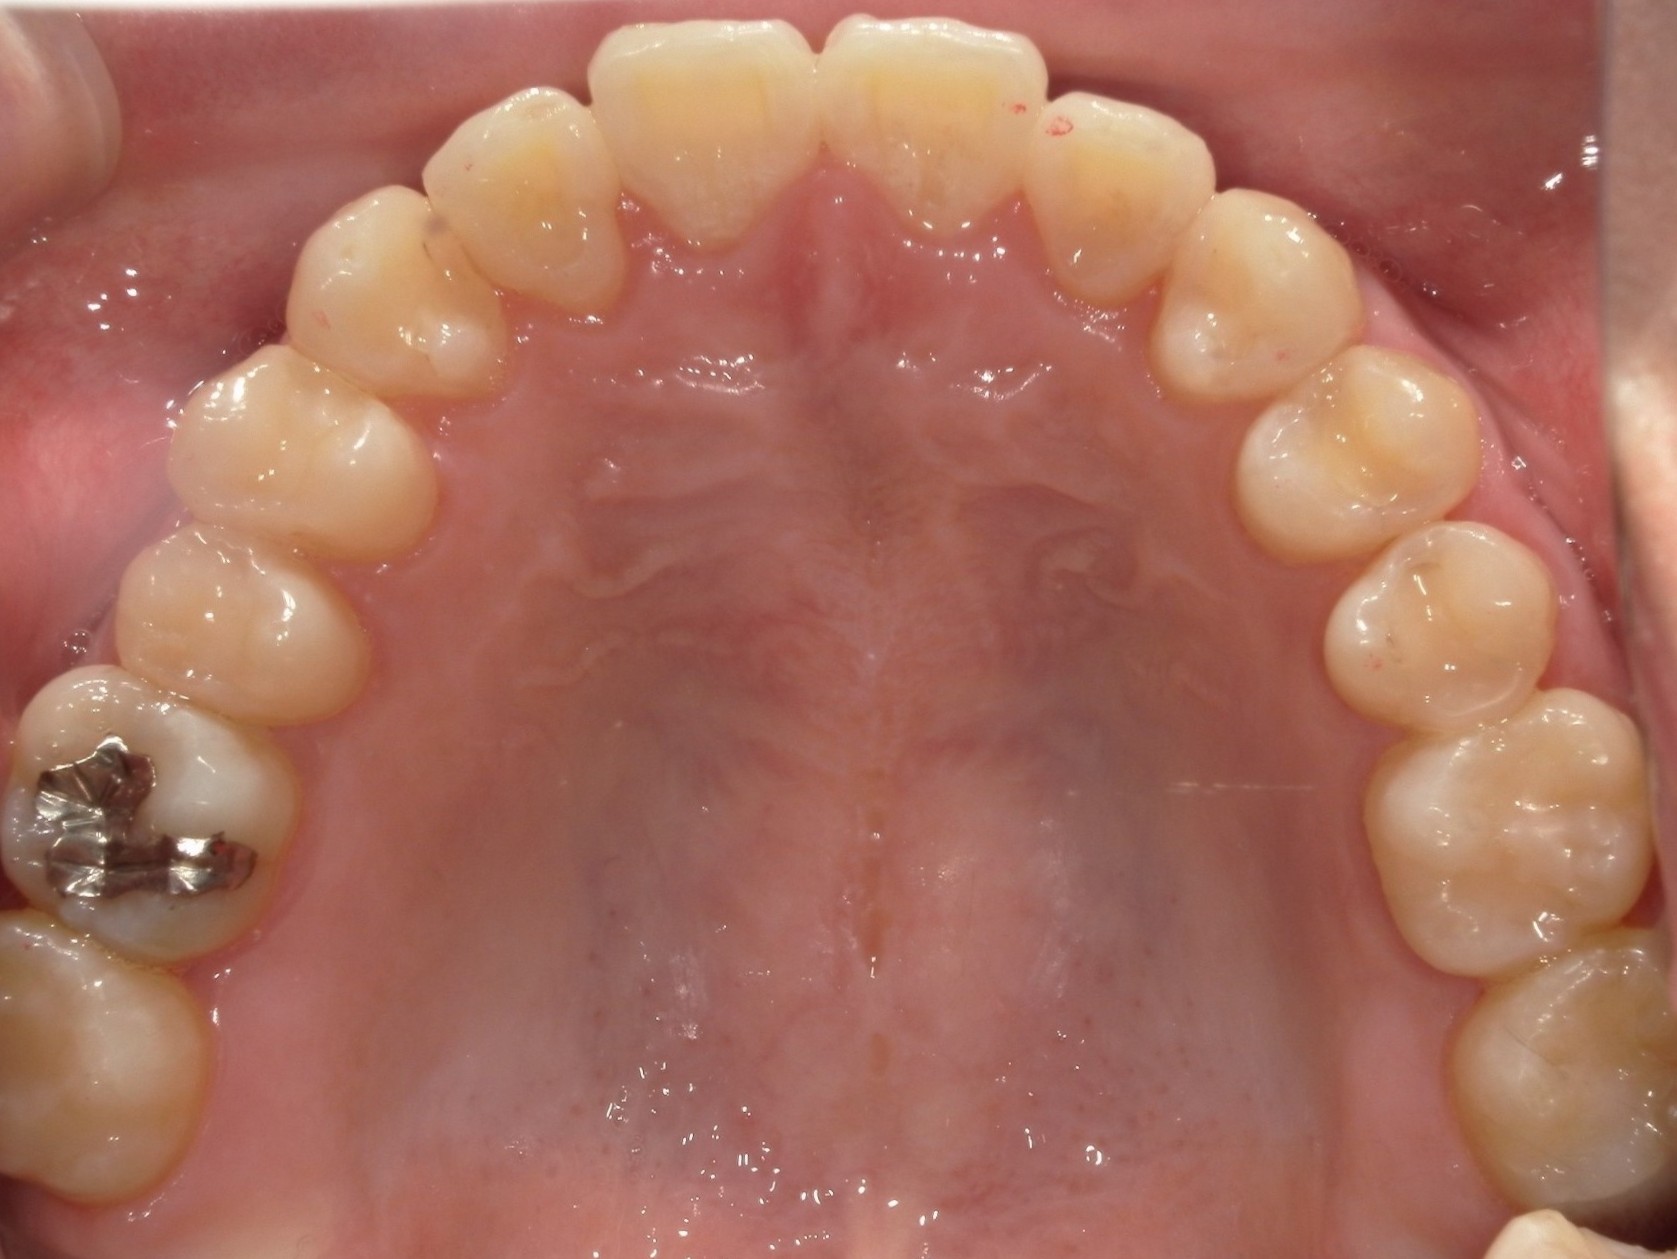

20代男性の方で、叢生・全体的な歯並び(不揃い・ガタガタ・不正咬合)が気になる患者様です。

歯が重なり合う状態は、見た目の問題だけではなく歯磨きが難しくなり虫歯や歯周病を引き起こすリスクにもなるため、インビザライン(重程度)矯正を行いました。

治療前